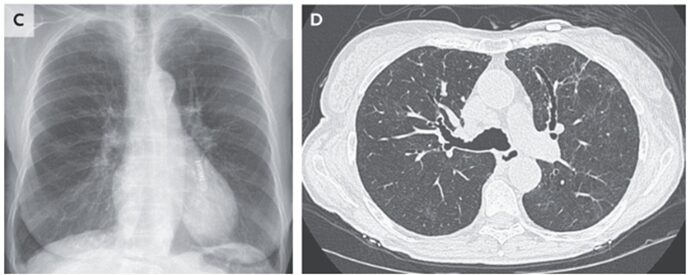

胸部Xpでは上肺野において透過性低下を認めた。

CT所見では上葉有意にGGOおよび牽引性気管支拡張を認めた。